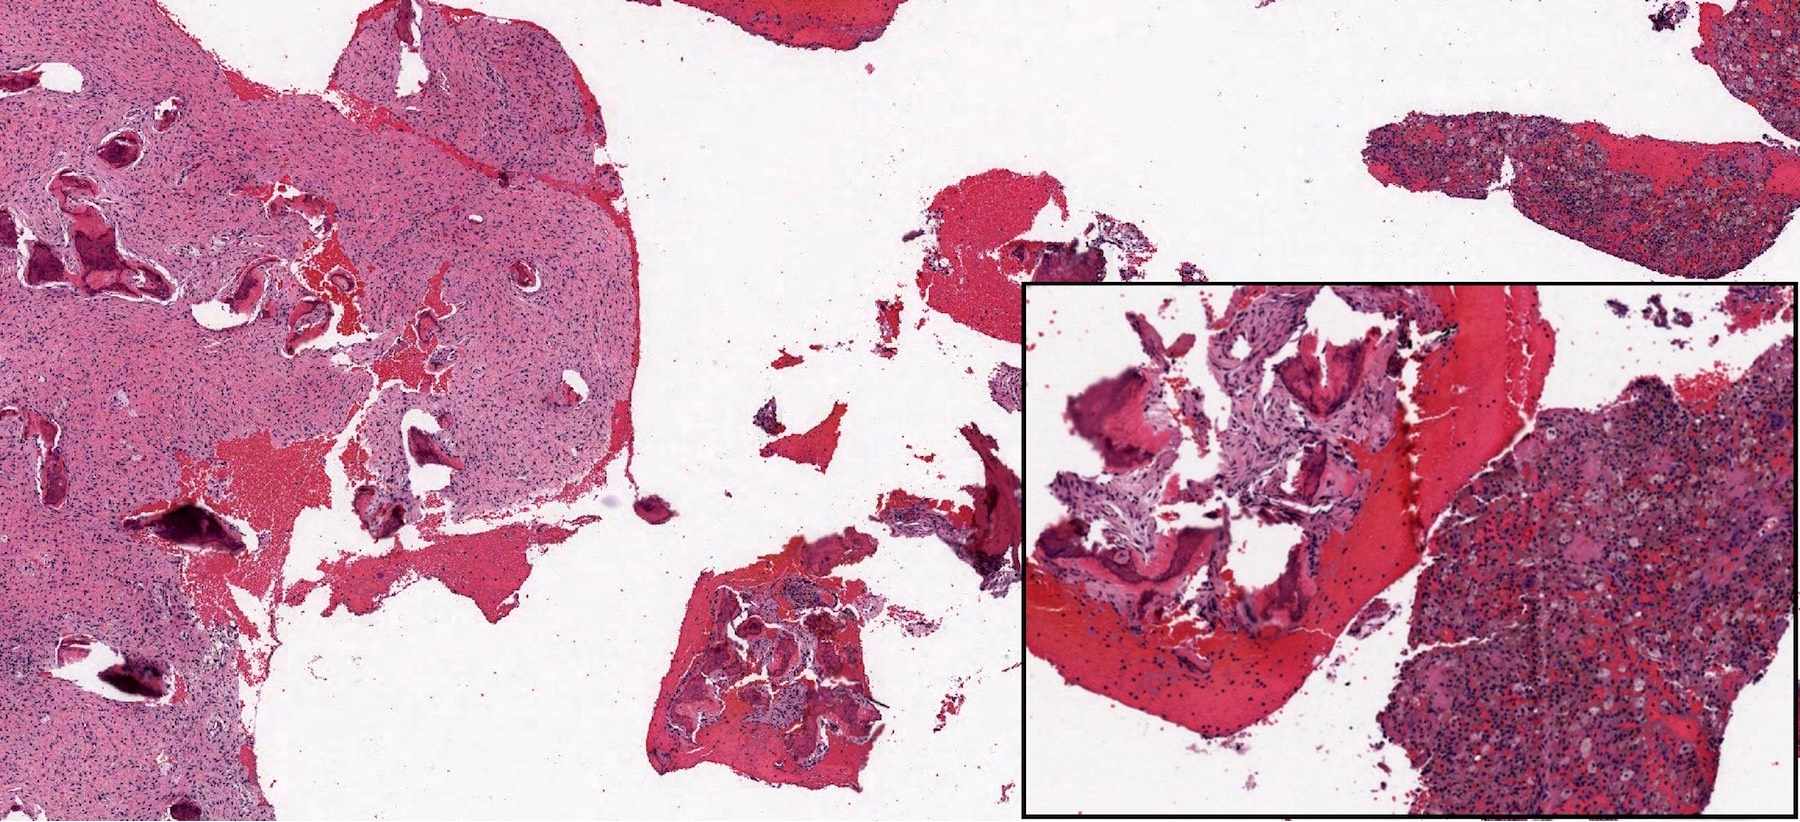

Microscopic (histologic) description

- Branching and anastomosing irregular trabeculae of woven bone ("C" and "S" shapes) with no conspicuous osteoblastic rimming

- No / rare osteoclasts

- Intervening fibrous stroma containing cytologically bland spindle cells, without prominent cytologic atypia

- Mitotic figures rare

- Stromal changes, including myxoid change and fatty metaplasia, may be seen in some cases (BMC Musculoskelet Disord 2003;4:20)

- Secondary aneurysmal bone cyst-like changes may also be seen (Turk Patoloji Derg 2018;34:234)

- Fibrocartilaginous dysplasia: uncommon variant containing variable proportions of cartilaginous differentiation and enchondral ossification (Am J Surg Pathol 1993;17:924)

- Growing collagen (Sharpey's fibers) may form perpendicular to the sites of bone formation but are not essential for diagnosis (Oral Dis 2017;23:697)

Microscopic (histologic) images